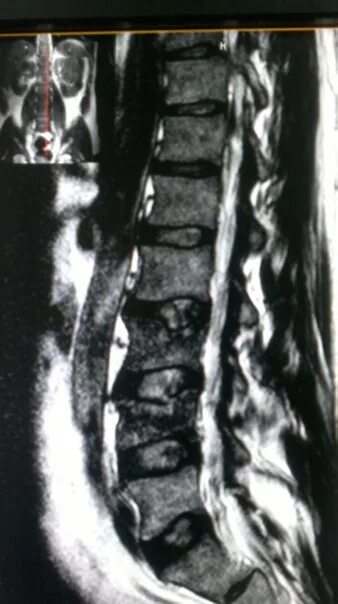

Метастазы в грудном отделе